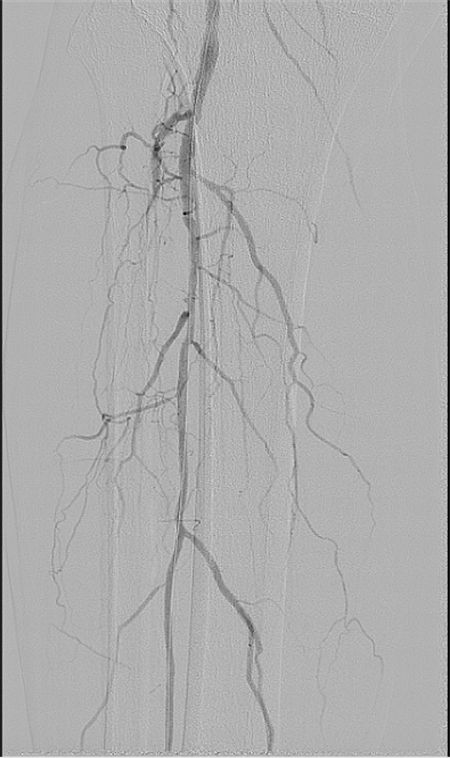

團(tuán)隊?wèi){借精準(zhǔn)的術(shù)前評估、規(guī)范的手術(shù)操作,成功為患者開通直達(dá)創(chuàng)面血管,改善創(chuàng)面供血。

術(shù)后患者恢復(fù)良好,足部溫度變暖,足跟部創(chuàng)面血運較前明顯改善,后期進(jìn)行中西醫(yī)結(jié)合創(chuàng)面換藥治療,未來可期。